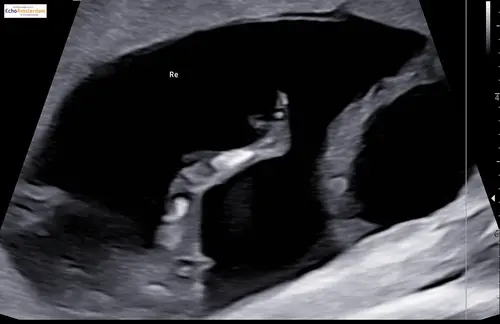

Wellicht dat ik hier tussen kom haha.. ziet iemand wat het is?😂